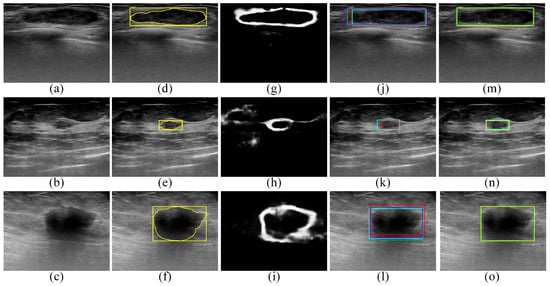

:1. Introduction

2.1. The Proposed Edge-Based Selection Method

2.2. Employing the Proposed Edge-Based Selection Method to Analyze the ROIs Generated by the Faster R-CNN, SSD, EfficientDet-D0, and CenterNet Models and Select the ROI That Enables the Effective Detection of the Region That Contains the Tumor

2.2.6. Employing the Proposed Edge-Based Selection Method to Select ROIs That Enable the Effective Detection of Regions That Contain Tumors